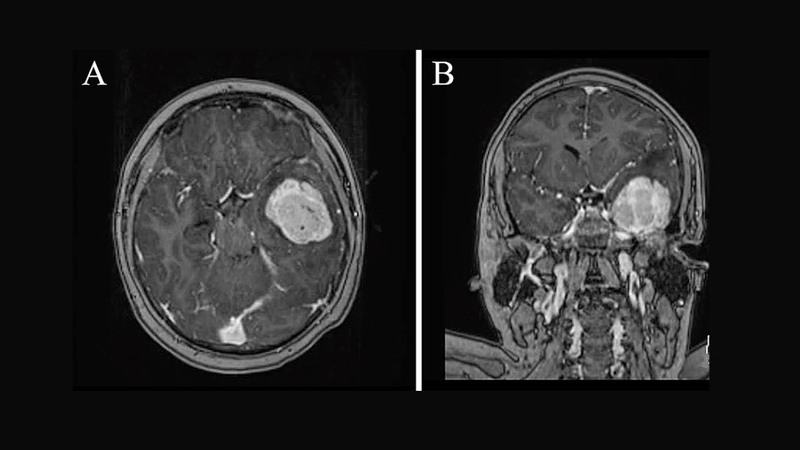

U màng não thái dương là một trong những dạng tổn thương nội sọ xuất phát từ lớp màng não bao phủ bề mặt não bộ. Việc nhận biết sớm các triệu chứng và áp dụng phương pháp điều trị phù hợp đóng vai trò quan trọng trong kiểm soát bệnh và hạn chế biến chứng.

Màng não là lớp màng bao bọc và bảo vệ não bộ, tuy nhiên, tại đây cũng có thể xuất hiện các khối u phát triển bất thường gọi là u màng não. Trong đó, u màng não thái dương thường gây ra các triệu chứng thần kinh điển hình do ảnh hưởng đến trung tâm ngôn ngữ và trí nhớ.

U màng não chiếm khoảng 25 - 35% tổng số các u não nguyên phát ở người lớn, là loại u não phổ biến nhất ở đối tượng này. Trong đa số các trường hợp u màng não là u lành tính, chiếm khoảng 90% trong tổng số ca. U màng não có thể phát triển ở nhiều vị trí khác nhau trong sọ, trong đó vùng thái dương là một vị trí khá phổ biến, đặc biệt tại vùng thái dương - bướm.

Ngoài ra, vùng thái dương còn nằm gần các cấu trúc giải phẫu quan trọng như dây thần kinh thị giác, dây vận nhãn, động mạch não giữa, và hố sọ giữa – nơi tập trung nhiều mạch máu và dây thần kinh sọ. U màng não thái dương, dù là u lành tính, vẫn có thể gây chèn ép vào các khu vực chức năng nhạy cảm.